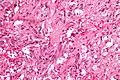

A gangliocytic paraganglioma is a rare tumour that is typically found in the duodenum and consists of three components: (1) ganglion cells, (2) epithelioid cells (paraganglioma-like) and, (3) spindle cells (schwannoma-like).[1]

GP consist of three components (1) ganglion cells, (2) epithelioid cells (neuroendocrine-like), and (3) spindle cells (schwannoma-like). The microscopic differential diagnosis includes poorly differentiated carcinoma, neuroendocrine tumour and paraganglioma.[1]

Intermed. mag. Very high mag.

Very high mag. Very high mag.